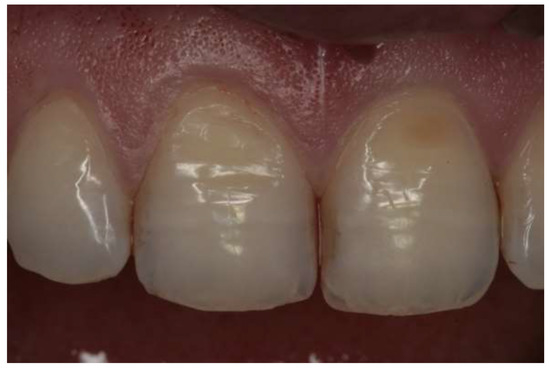

- Grade 0: no erosive changes;

- Grade 1: initial loss of enamel texture;

- Grade 2: visible loss of hard tissues under 50% of the surface; and

- Grade 3: visible loss of hard tissues over 50% of the surface.